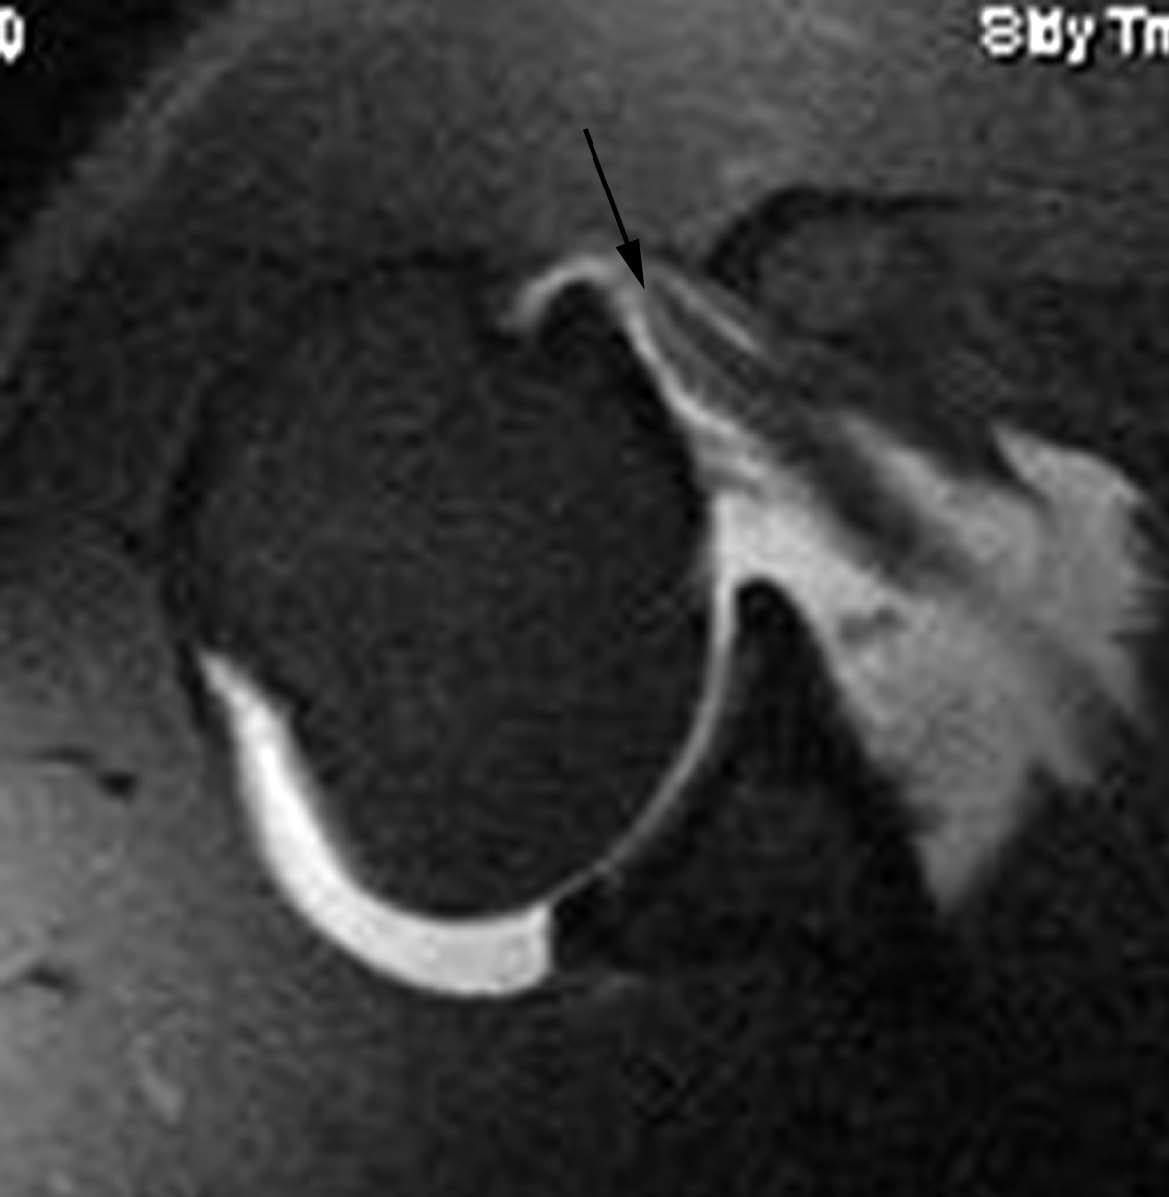

Lesión de Perthes

La lesión de Perthes es similar a la de Bankart, con la excepción de que no existe rotura capsuloperióstica, aunque el periostio puede estar separado del borde anterior del margen glenoideo (fig. 10). Esta lesión puede ser difícil de visualizar, incluso con artrorresonancia, a menos que se obtengan imágenes con la posición de abducción y rotación externa (ABER). En un estudio de 10 casos, verificados quirúrgicamente, Wisher et al17 comprobaron que el 50% de las lesiones de Perthes sólo podían visualizarse en la posición de ABER.

Fig. 10.--Lesión de Perthes. Artrorresonancia T1 con saturación grasa en posición ABER (abducción y rotación externa), donde se observa un arrancamiento parcial del labio glenoideo (flecha) con conservación de la unión capsuloperióstica.